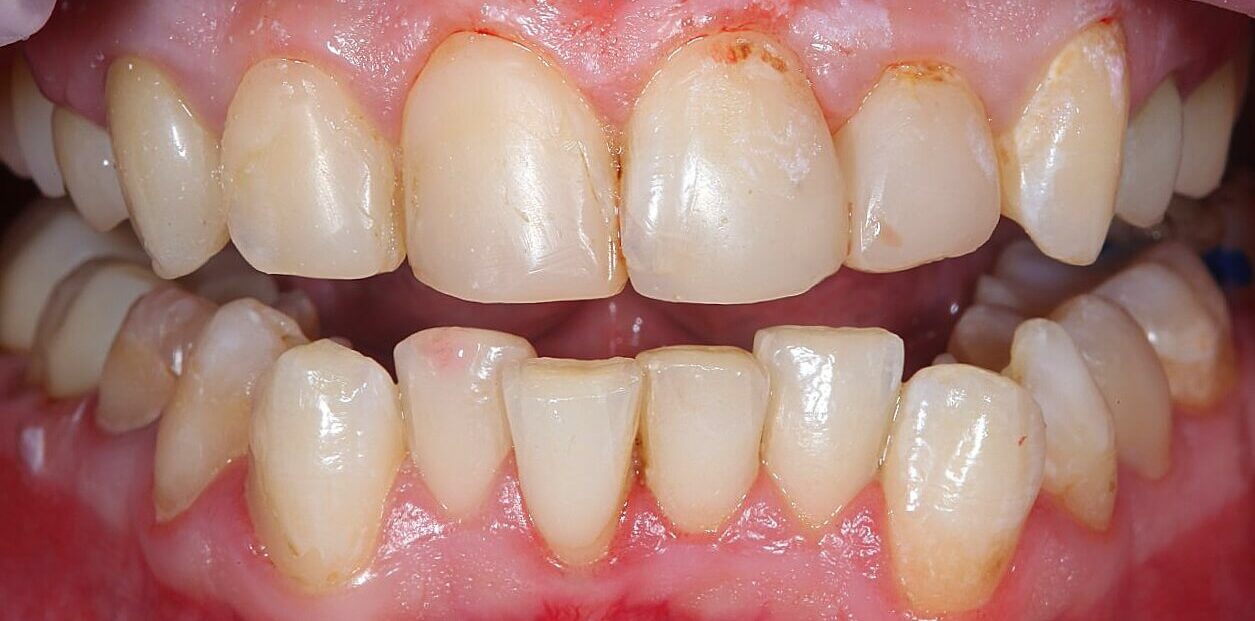

Художня реставрація верхнього зубного ряду

Вихідна ситуація: незадовільний колір зубів, стертість емалі, старі реставрації, що потребували заміни.  Побажання пацієнта: природний вигляд, максимальне збереження наявних здорових тканин зубів і небажання встановлювати коронки. Оцінивши наявну ситуацію і побажання пацієнта ми запропонували реставрацію зубів сучасними композитними матеріалами. Як наслідок пацієнт отримав відновлений природний колір та форму зубів.

Категорія: Художня реставрація